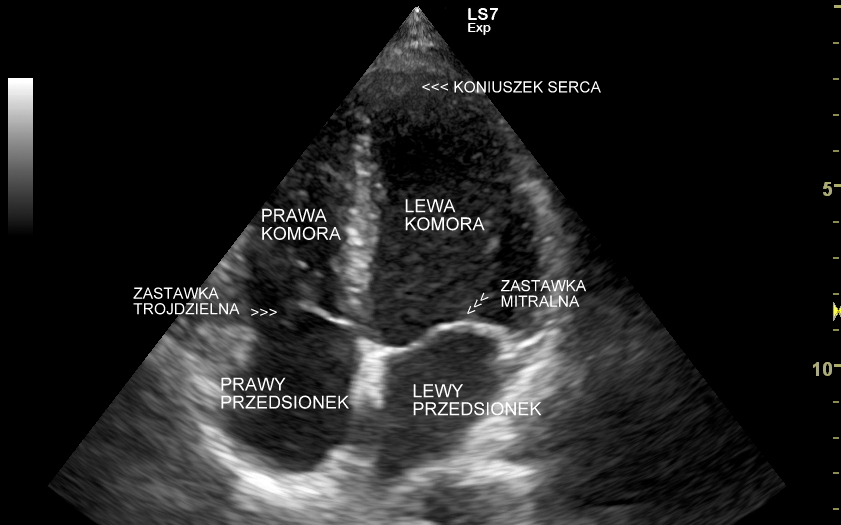

Badanie echokardiograficzne, nazywane także echo serca lub USG serca jest jedną z podstawowych metod diagnostyki kardiologicznej. W badaniu tym ocenia się zarówno morfologię narządu, jak i jego funkcję w postaci pomiarów wielkości jam serca, grubości mięśnia sercowego, czynności skurczowej oraz rozkurczowej lewej i prawej komory, oceny funkcji zastawek serca, wyglądu wsierdzia, osierdzia, a także w postaci pomiarów aorty, poszukiwania obecności patologicznych objawów sercowych związanych z chorobami innych narządów (np. choroby płuc, nadciśnienie tętnicze).

Specjalista chorób wewnętrznych z wieloletnią praktyką kardiologiczną i naczyniową. Szkolenie USG serca odbywał w Pododdziale Kardiodiagnostyki w Klinice Chirurgii Serca Akademii Medycznej we Wrocławiu. Jeden z najbardziej doświadczonych sonografistów w Polsce. Posiada ponad 25-letni staż kliniczny i szkoleniowy w Polsce oraz zagranicą (Wielka Brytania, Niemcy, Austria, Włochy). Wykonał ponad 40.000 badań USG. Wprowadził do rutynowego zastosowania w Polsce takie procedury diagnostyczne jak USG z kontrastem (CEUS) oraz multiparametryczne badania USG (MPUS). Certyfikowany lekarz Polskiego Towarzystwa Ultrasonograficznego z zakresu badań naczyniowych. Na co dzień dr Szczepański zajmuje się przeglądami zdrowia oraz specjalistyczną diagnostyką z zakresu chorób wewnętrznych i serca.